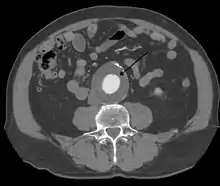

The diagnosis of an abdominal aortic aneurysm can be confirmed by the use of ultrasound. Rupture may be indicated by the presence of free fluid in the abdomen. A contrast-enhanced abdominal CT scan is the best test to diagnose an AAA and guide treatment options.[10]

A large, rapidly expanding, or symptomatic aneurysm should be repaired, as it has a greater chance of rupture. Slowly expanding aortic aneurysms may be followed by routine diagnostic testing (i.e.: CT scan or ultrasound imaging).

For abdominal aneurysms, the current treatment guidelines for abdominal aortic aneurysms suggest elective surgical repair when the diameter of the aneurysm is greater than 5 cm (2 in). However, recent data on patients aged 60–76 suggest medical management for abdominal aneurysms with a diameter of less than 5.5 cm (2 in).[19]